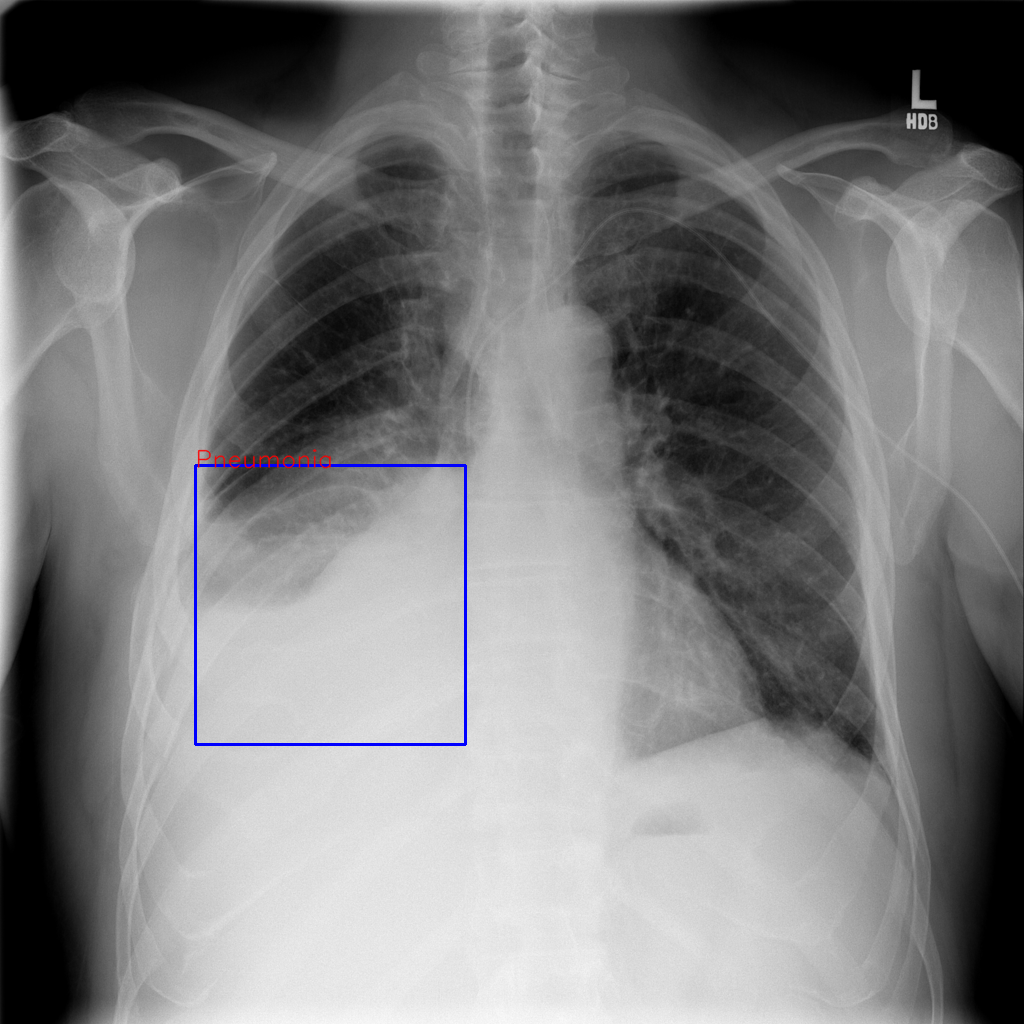

\rowcolorgray!10     Example 1: Abnormality detection.

[Uncaptioned image]   Does the lung look abnormal?

[Uncaptioned image] Ground truth: Yes, the lung appears abnormal as there are irregularities in the lung fields that may indicate potential pathology. The presence of unusual opacities or changes in the lung structure can suggest conditions such as infection, inflammation, or other lung diseases. [Uncaptioned image]

SilVar-Med (Llama 3.1): Yes, the lung appears abnormal due to the presence of irregularities in the lung fields, which may indicate potential pathology such as infection, inflammation, or other lung conditions. The overall lung structure shows signs of asymmetry or density changes that deviate from normal anatomy. These findings warrant further investigation to determine the underlying cause.

GPT-4o mini: The lung appears to be within normal limits based on the provided X-ray image. There are no obvious signs of abnormalities such as masses, infiltrates, or significant opacities. The lung fields are clear, and the vascular markings are normal, indicating healthy lung tissue. However, a definitive assessment should be made by a qualified radiologist for a comprehensive evaluation.

Gemini 1.5 Flash: Based on the provided chest X-ray, the lungs appear normal. There is no visible evidence of infiltrates, masses, or pneumothorax. The lung fields demonstrate normal aeration and the heart size appears within normal limits. Further evaluation may be necessary depending on the clinical presentation.

Table 9: Comparison of prediction between our models and the other speech-driven model on the reasoning abnormal detection. Unlike GPT-4o and Gemini 1.5 Flash, our SilVar-Med is an end-to-end speech-driven VLM. For more demonstration, please visit SilVar-Med.